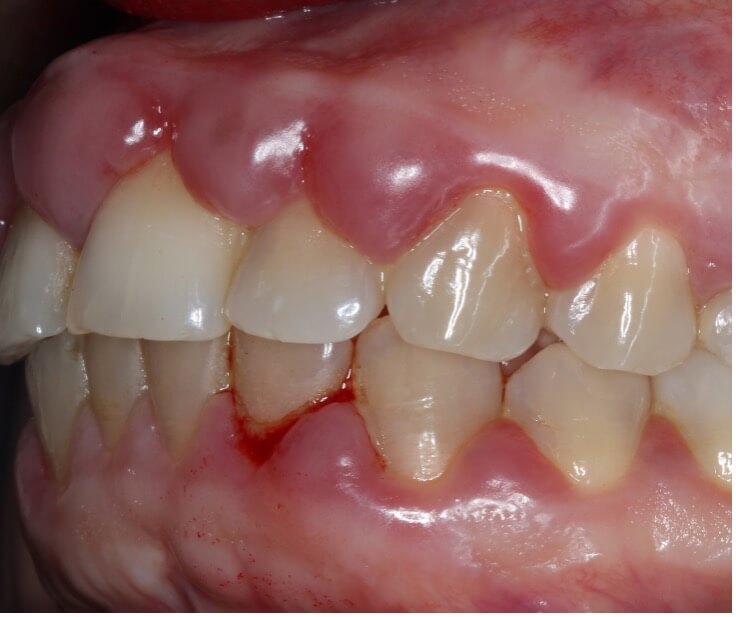

Oral health significantly impacts pregnancy outcomes and maternal well-being. Poor oral health during pregnancy has been linked to several adverse effects, including preterm delivery, low birth weight babies, and pre-eclampsia [104]. Several studies have demonstrated the possible translocation of oral bacteria into the placenta, which may play a role in complications during pregnancy [105, 106]. The hormonal changes during pregnancy, particularly increased levels of estrogen and progesterone, make women more susceptible to gum problems like gingivitis (Fig. 8) and periodontitis [107]. A study shows that pregnant women are more prone to oral diseases: they are 1.97 times more likely to develop dental caries [107] and nearly 47% suffer from periodontitis [42].

Fig. 8.

Gravidic gingivitis in a patient 6 months pregnant, manifested by hypertrophy and bleeding of the gums.